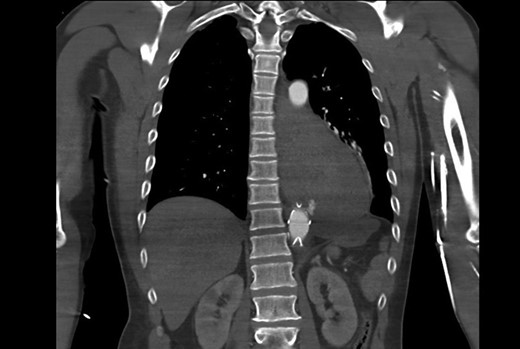

The purpose of this case report is to describe the clinical course of a 57-year-old male who presented with acute onset of massive haematemesis and hypovolaemic shock. His medical history was remarkable for a trans-hiatal oesophagectomy and gastric pull-up for adenocarcinoma 15 years prior. After initial fluid resuscitated, oesophago-gastro-duodenoscopy (OGD) was performed which was complicated by cardiac arrest. He was intubated and fluid resuscitated until haemodynamically stable. Computed tomography aortography (CTA) demonstrated an aorto-oesophageal fistula (Fig. 1). A rapid decision was made to proceed with a TEVAR limited to that segment of aorta using Cook Zenith Alpha 24/105 stent graft. The procedure was successful. The patient was later offered definitive procedure, which he refused. Follow-up OGD after 4 weeks revealed a gastric ulcer, with no abnormal cells on histology, for which he was placed on high dose proton-pump inhibitor.

CT aortogram showing the extravasation of contrast into the stomach.